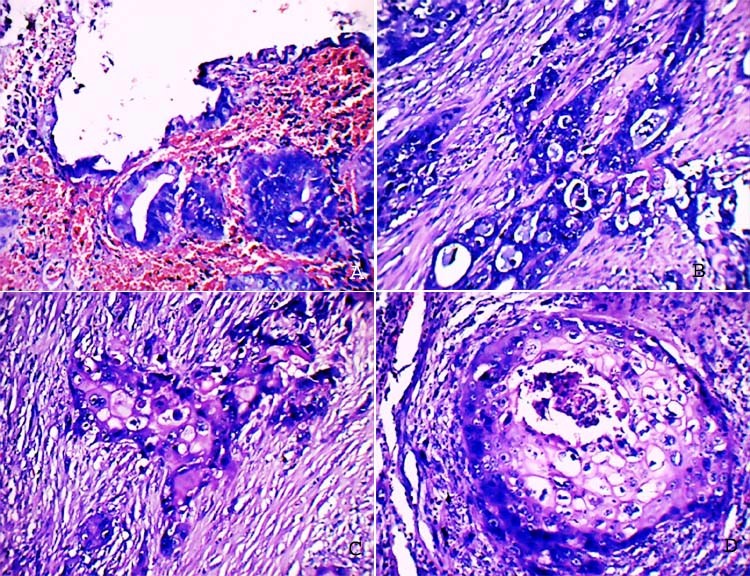

Carcinoma of the gallbladder is the most common malignancy of the biliary tract. Although adenocarcinomas account for more than 90% of gallbladder cancers, the incidence of adenosquamous carcinomas (ASCs) is only approximately 5%. ASCs have aggressive biological behavior due to their potential for direct extension into the liver and neighboring structures like stomach, duodenum, and transverse colon. In most cases, the disease would have advanced at the time of diagnosis and the prognosis might be dismal when compared to ordinary adenocarcinoma of the gallbladder. We present here a rare case of ASC of gallbladder in a 59-yr-old female who presented with right upper abdominal pain.